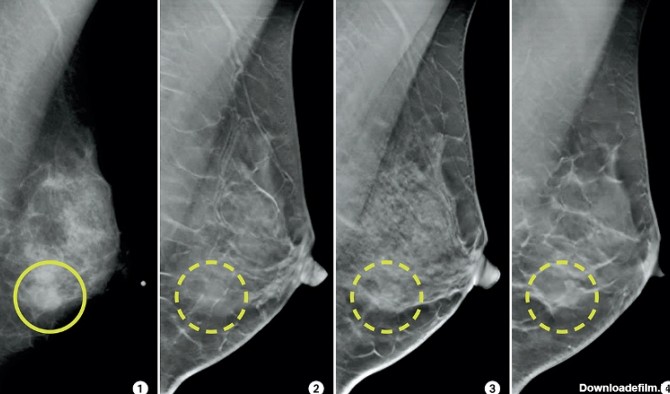

ماموگرافی توانایی پزشک را در تشخیص توده های کوچک افزایش می دهد. وقتی بیماری سرطان در مراحل اولیه باشد احتمال درمان کامل بیماری بسیار بالا است.. استفاده ازماموگرافی تشخیص رشد غیر طبیعی بافت درون مجاری شیری را امکان پذیر می سازد. این تومورهای سرطانی در صورتیکه در مراحل اولیه جراحی و خارج شوند آسیب چندانی برای فرد ایجاد نمیکنند. ماموگرافی تنها روش ثابت شده تشخی ... | انجام کلیه امور مربوط به سونوگرافی، رادیولوژی، ماموگرافی، پانورکس و سنجش تراکم استخوان به صورت دیجیتال واقع در غرب استان تهران (شهرک اکباتان)

ماموگرافی شکل و ظاهر سرطان سینه در ماموگرافی